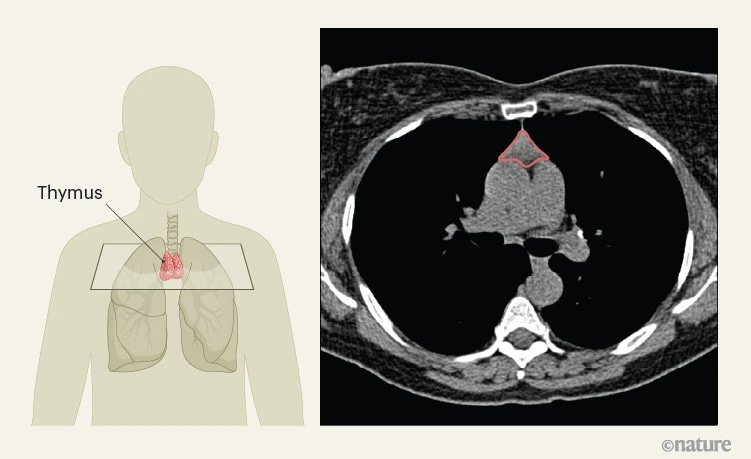

“The thymus is an organ in the chest that produces T cells, essential components of the immune system. However, after peaking in size in adolescence, the thymus progressively shrinks as people age, leaving its relevance to adult health unclear.” Using AI-based imaging in studies of over 5,000 individuals, researchers found that thymus health in adults predicts overall health, disease risk, and response to cancer immunotherapy.

From: https://www.nature.com/articles/d41586-026-00633-6